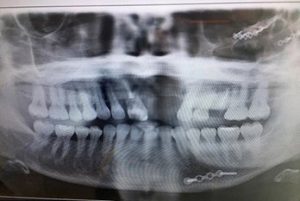

وتورم رأس ساندرا بسبب الحادث وأصبح بحجم كرة السلة، كما تشوه وجهها بالكامل، واعتقد الأطباء ستخسر أسنانها وتبقى بدونها لفترة طويلة، هذا الأمر دفع ساندرا للتفكير في الانتحار، وقالت: “بعد الحادث فكرت بالموت كل يوم، لقد كرهت حياتي وأنا أخفي وجهي من العالم لمدة ست سنوات”.

وأضافت: “أسناني تؤلمني بشكل فظيع، ووصل الحد للتحقق من وجود أسناني صباح كل يوم أمام المرآة”.

وأجرت ساندرا 30 عملية جراحية لتتمكن بعدها من الخروج من منزلها.